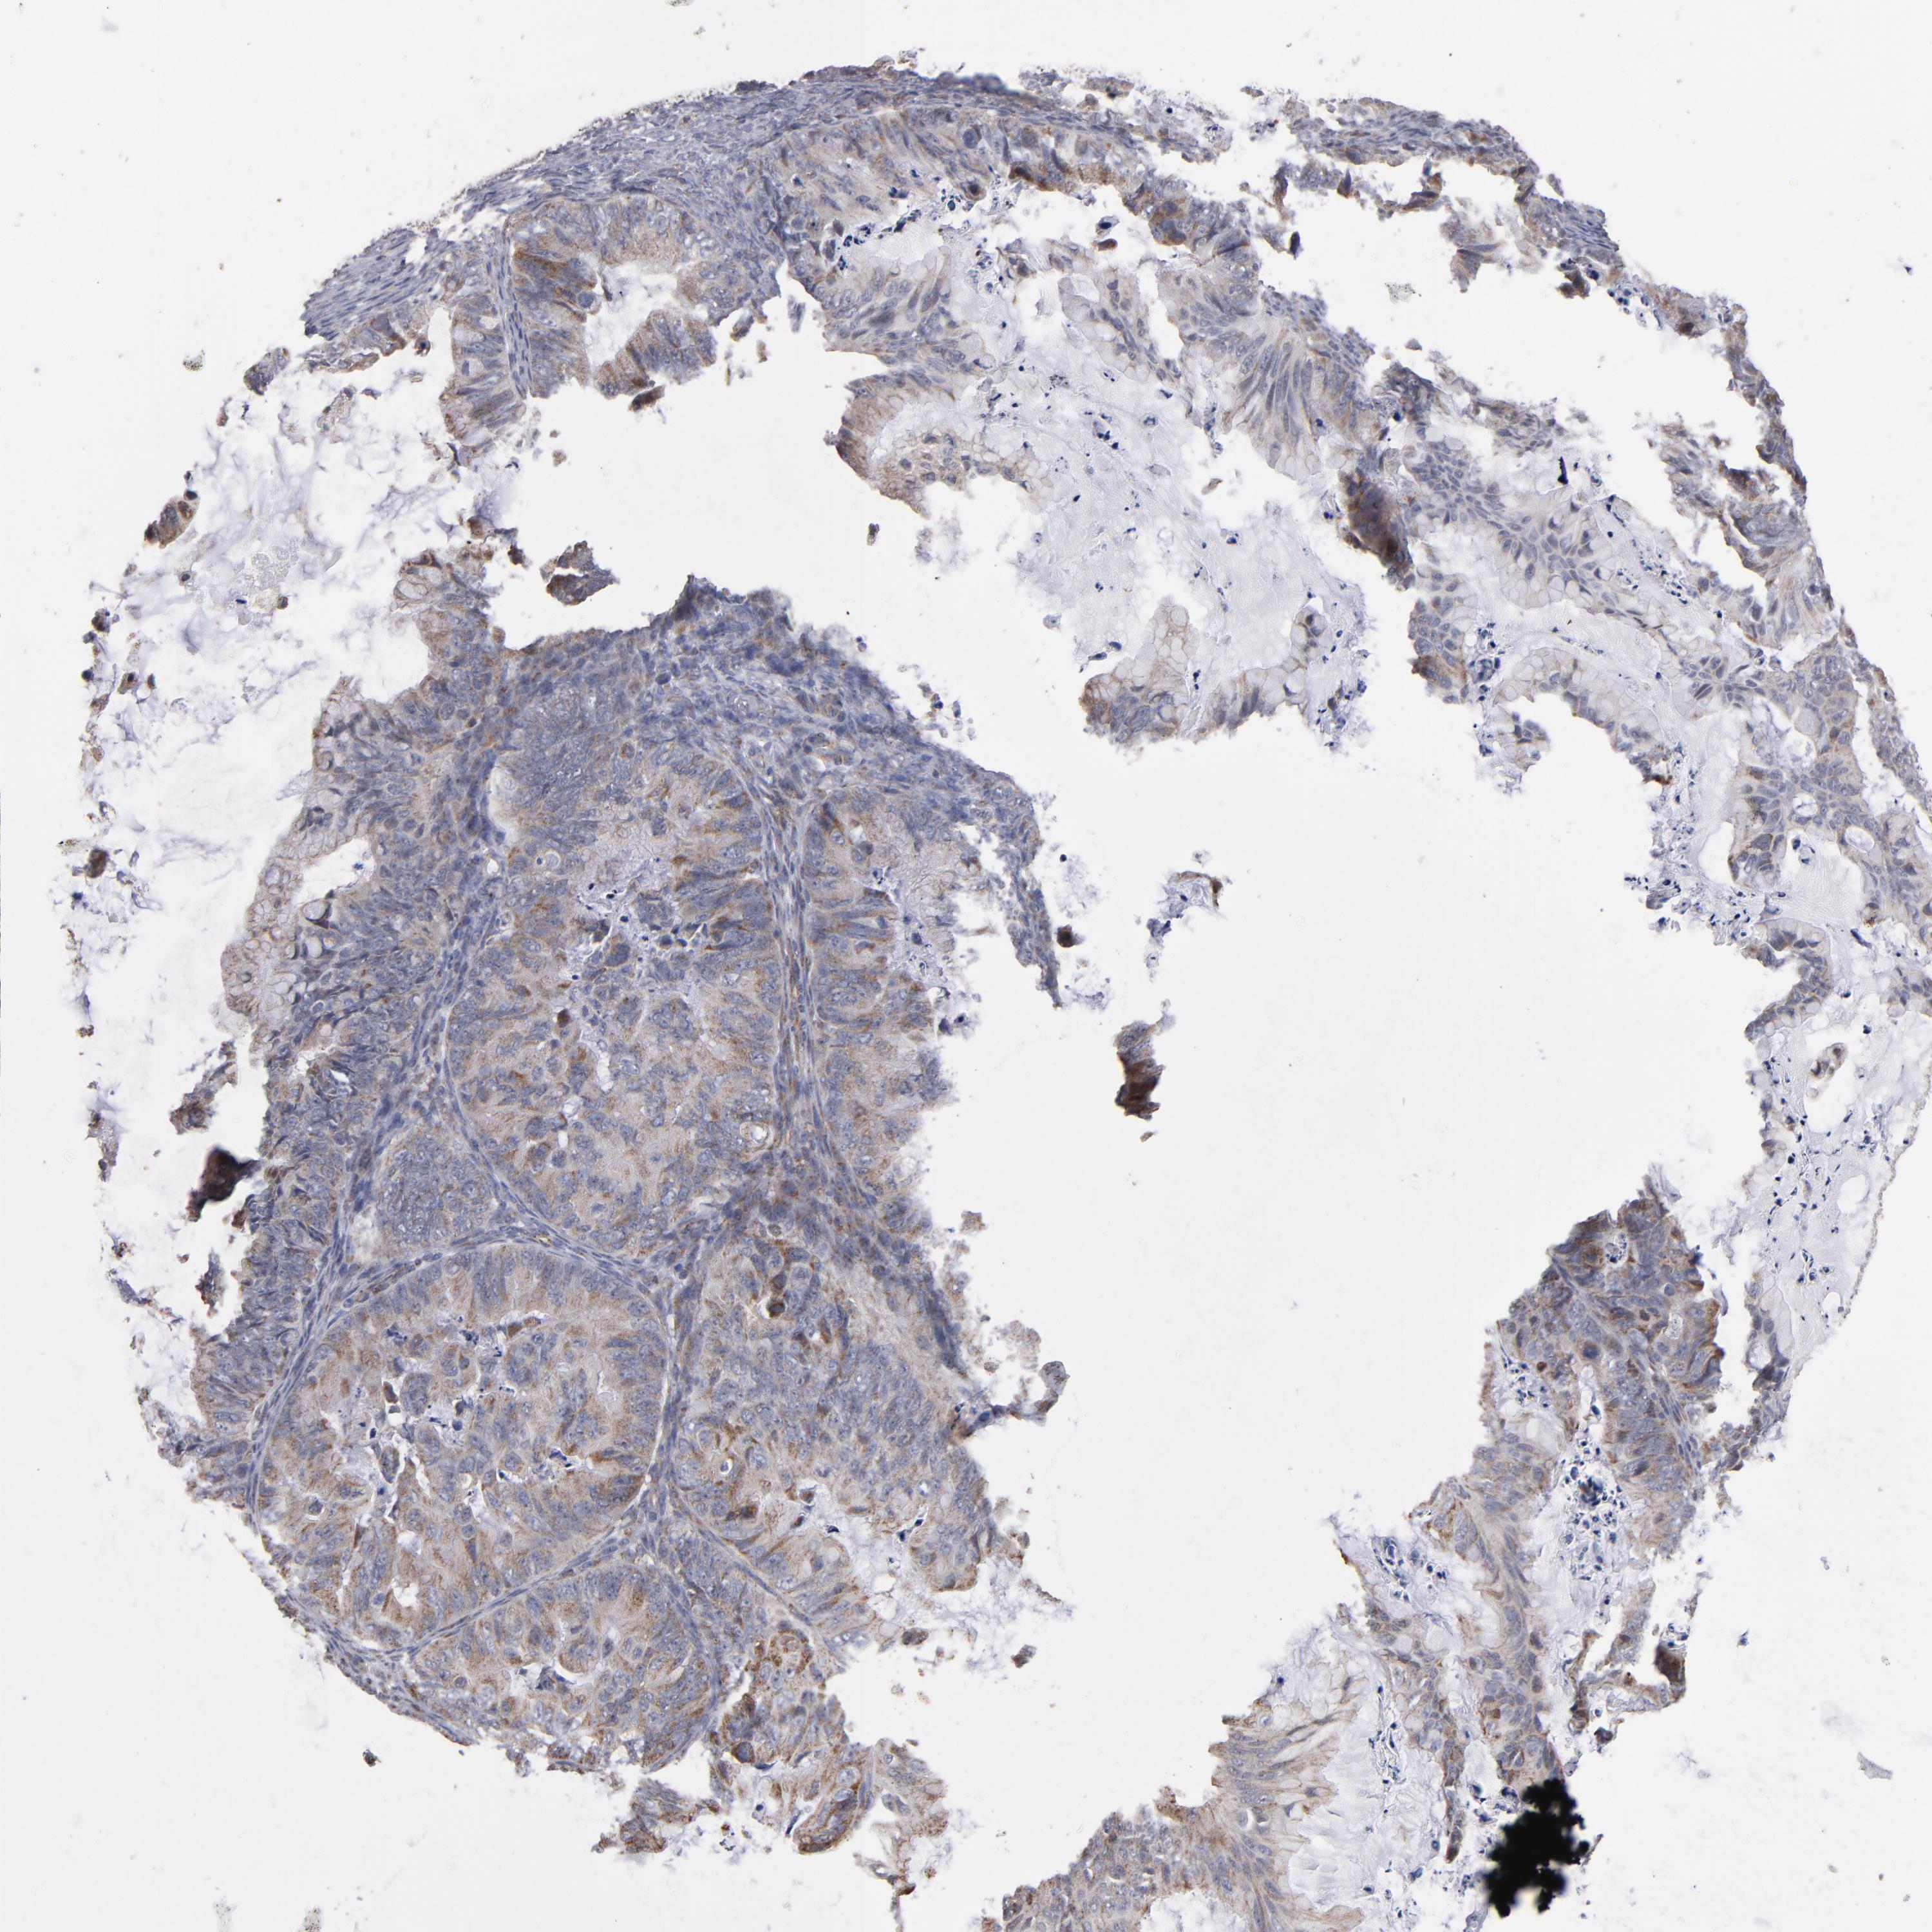

OVARIAN CANCER - Protein expressioni

A mouse-over function shows sample information and annotation data. Click on an image to view it in a full screen mode. Samples can be filtered based on level of antibody staining by selecting one or several of the following categories: high, medium, low and not detected. The assay and annotation is described here.

Note that samples used for immunohistochemistry by the Human Protein Atlas do not correspond to samples in the TCGA dataset.

Antibody stainingi

Antibody staining in the annotated cell types in the current human tissue is reported as not detected, low, medium, or high, based on conventional immunohistochemistry profiling in selected tissues. This score is based on the combination of the staining intensity and fraction of stained cells.

Each image is clickable and will lead to virtual microscopy that enables deeper exploration of all samples and also displays staining intensity scores, fraction scores and subcellular localization as well as patient and tissue information for each sample.

Antibody HPA002893

Staining

High

Medium

Low

Not detected

Intensity

Strong

Moderate

Weak

Negative

Quantity

>75%

75%-25%

<25%

None

Location

Nuclear

Cytoplasmic/membranous

Cytoplasmic/membranous,nuclear

Cystadenocarcinoma, serous, NOS

Cystadenocarcinoma, mucinous, NOS

Carcinoma, endometroid